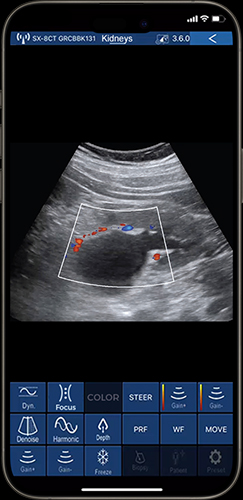

In the Internal Medicine department, 80-element ultrasound devices are frequently used to evaluate abdominal organs, such as the liver and kidneys. It allows internists to identify hepatomegaly, cirrhosis, or fatty infiltration, and characterize simple hepatic cysts versus focal liver lesions based on echogenicity and morphology. In kidney assessments, an 80-element ultrasound device helps clinicians determine the renal size and features such as cortical thickness and cystic formations, aiding in the diagnosis of conditions like renal artery stenosis or hydronephrosis. Additionally, the 80-element ultrasound transducer assists in monitoring changes in organ size over time in chronic conditions, supporting healthcare providers in long-term patient management.